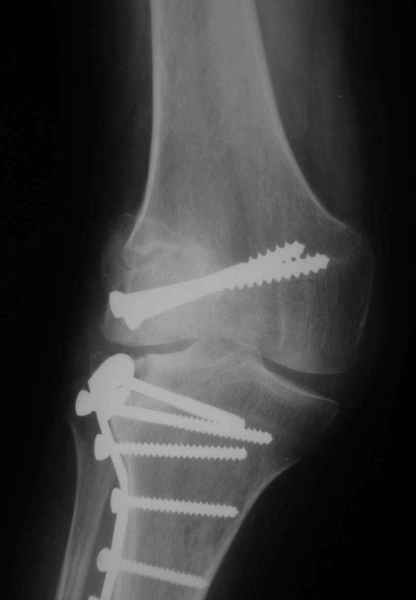

Уважаемый Евгений ! Спасибо за ответ, но мне представляется, что в нашем случае основной проблемой является не столько прогрессирующий вальгус конечности, сколько несросшийся перелом мыщелка бедра и дефект мыщелка большеберцой кости - вероятно первичная репозиция выполнялась без пластики.

Может стоит сначала добиться сращения наружного мыщелка бедра( костная пластика) и коррекции оси?

Мне представляется, что прогрессирующий вальгус и обусловлен несросшимся переломом мыщелка бедра (томограммы -зона межфрагментарного склерозирования), а циклические нагрузки на сустав во время ходьбы усугубляют ситуацию. Как вы думаете, в этой ситуации насколько вероятен риск развития аваскулярного некроза мыщелка бедра?

Относительно "рубцовой подушки" я имел в виду остатки мениска ( частично вколоченного в дефект мыщелка и фрагменты хряща), все таки на рентгенограммах суставная щель в этом отделе чем то заполнена. Что касается некроза мыщелка бедра, то мне кажется он уже наступил - томограмма ноябрь5.

С учетом всего сказанного - наличия прогессирующего вальгуса конечности, довольно приличного объема движений, имеющегося, вероятно, некроза мыщелка бедра, наиболее рациональным представляется удалить пластину с б\б кости, произвести остеотомию б\б кости с коррекцией вальгуса, разгрузив тем самым наружный отдел сустава, и синтезировать фрагменты голени накостным фиксатором. Максимально тано начать восстановление движений в суставе. Скорее всего рано или поздно речь о протезировании всеже возникнет, но мы хотя бы будем иметь приличную ось конечности.